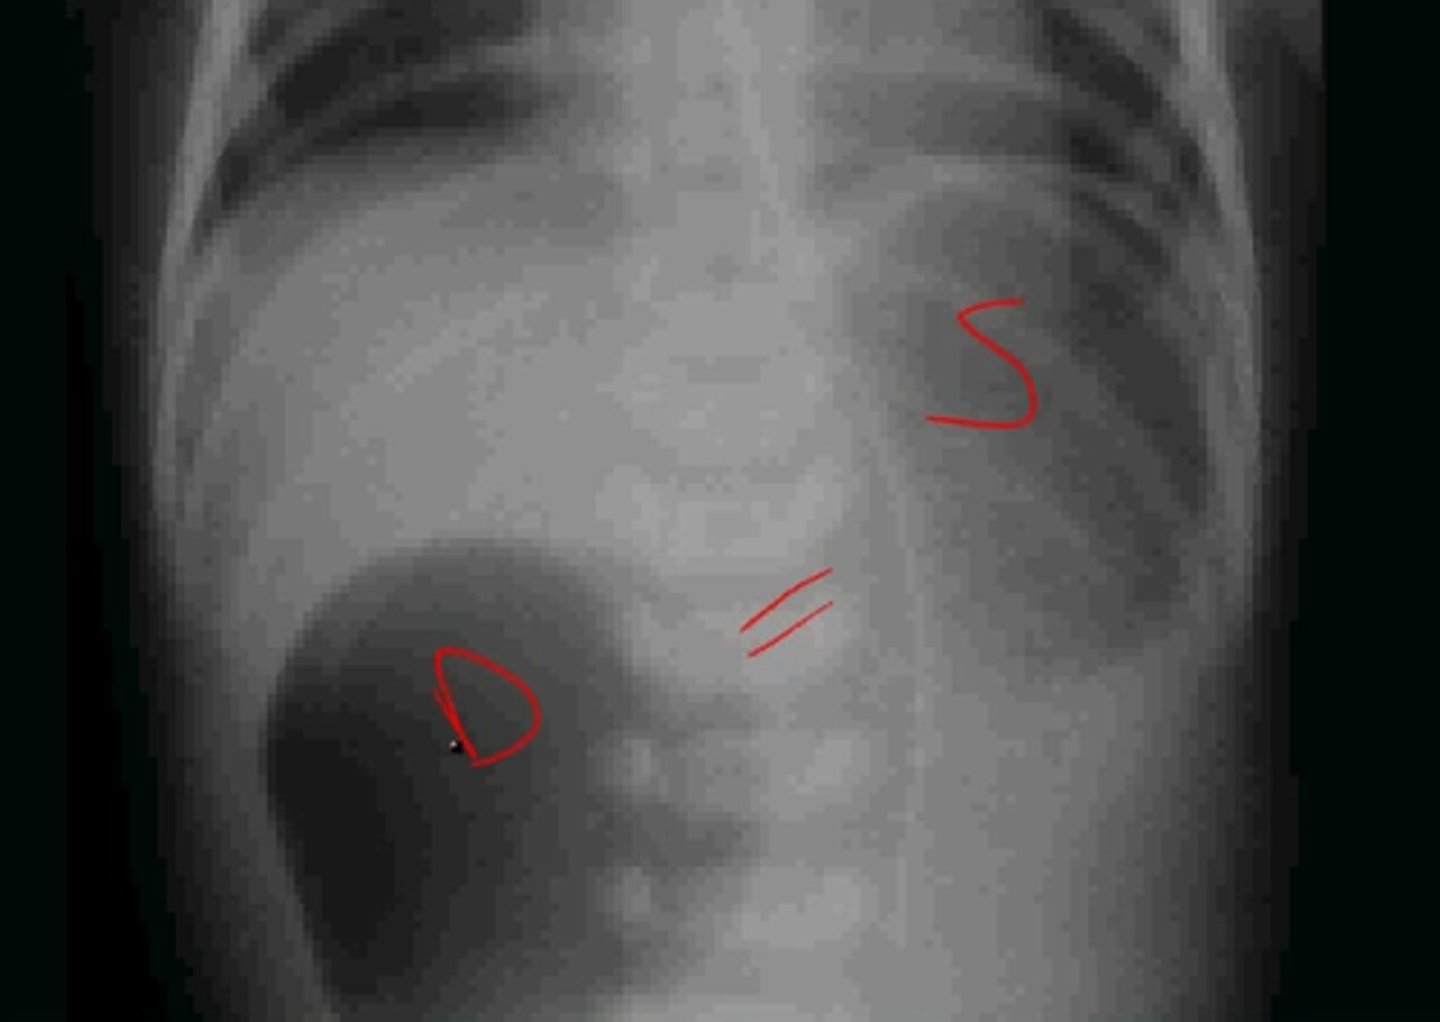

What is duodenal atresia, & what is it often associated with? What is a way we may detect this before birth?

Congenital absence or complete closure of part of the duodenum; trisomy's (especially Down syndrome); fetal US may show polyhydramnios

What are some s/sxs of duodenal atresia?

Bilious vomiting, failure to pass meconium (FPM), failure to thrive (FTT), scaphoid abdomen w/ epigastric distension

What is the best initial diagnostic test for duodenal atresia, & what will be seen? What condition do we need to absolutely r/o before diagnosing this?

Abdominal x-ray - shows "double bubble" sign; need to r/o volvulus (contrast enema can d/dx these)